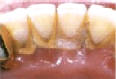

Zubní kámen se vytváří buď nad dásní nebo pod ní. Mechanicky dráždí okolní tkáně,zhoršuje ústní hygienu a usnadňuje usazování a množení škodlivých bakterií. Tím prohlubuje onemocnění dásní a vede k parodontitidě. K jeho odstranění se používá ultrazvukový přístroj (scaler), ruční nástroje (srpky a kyrety) nebo laser. U citlivých pacientů nebo při rozsáhlém postižení je možno aplikovat povrchovou či lokální anestezie. Po zákroku dentální hygienistka zuby vyleští speciální pastou, aby zarovnala nerovnosti ve sklovině a znesnadnila tvorbu nového povlaku na zubech.

Dentální hygiena - odstranění zubního kamene

před ošetřením

Dentální hygiena - po odstranění zubního kamene

po ošetření části zubů